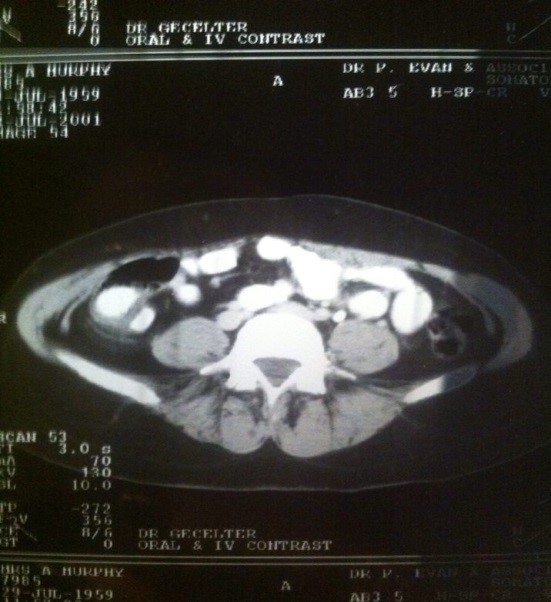

Following the ultra-sound, the radiologist called in two other doctors, one of them held my hand told tell me there is a very large mass in my abdomen measuring 15cm which needs to be treated immediately. I went back to the gynaecologist and he informed me that he had left a message for the urologist to call him. Fortunately, he called him back whilst I was sitting there and he arranged to see me 7am the next morning (Thurs.) for a CT scan.

Following the scan, the doctor phoned with the results around 6pm. He confirmed the tumour was malignant and that I was to undergo a seven-hour operation the next day. I explained that I had to first finishing making my daughter Kimberley’s debutante ball dress for the following Friday, so could only go in for the operation on Monday, which I did. I underwent the operation and was left with a severe scar from top left, under my breast, to the top of my right hip but I was discharged in time to see my daughter go off to the ball in her limousine. Remarkably, within two months I was back in work.

Fast forward 11 years to November 2017. I’m 58 years young, and I’m working as an Office Manager for Carillion Rail. It was then I felt that niggly pain again, but this time it was also under my left rib cage. Straight away I booked to see my local GP who took a blood test and sent me for an ultra-sound. Following the scan, the radiologist instructed me to go to my GP immediately and that he was going to call them to discuss the results of the scan. When I arrived at the surgery, the doctor explained that the scan showed two masses near my pancreas and that we need to arrange a CT scan immediately. It was a Wednesday and my Doctor said she will try to get an appointment on the NHS but as I had private medical aid I said I would try that route too and see who gets an appointment first. She phoned me on the Friday and told me she’d had no luck as yet, but I’d managed to get an appointment with a private urologist for the following Monday where he arranged for me to have the scan. On our second appointment he informed us that there weren’t just two masses but one primary on my kidney and four in my pancreas. He explained my case was to be discussed in an MDT meeting which turned out to be the longest wait; three-weeks in total. I have coloured them in yellow in the pic below.